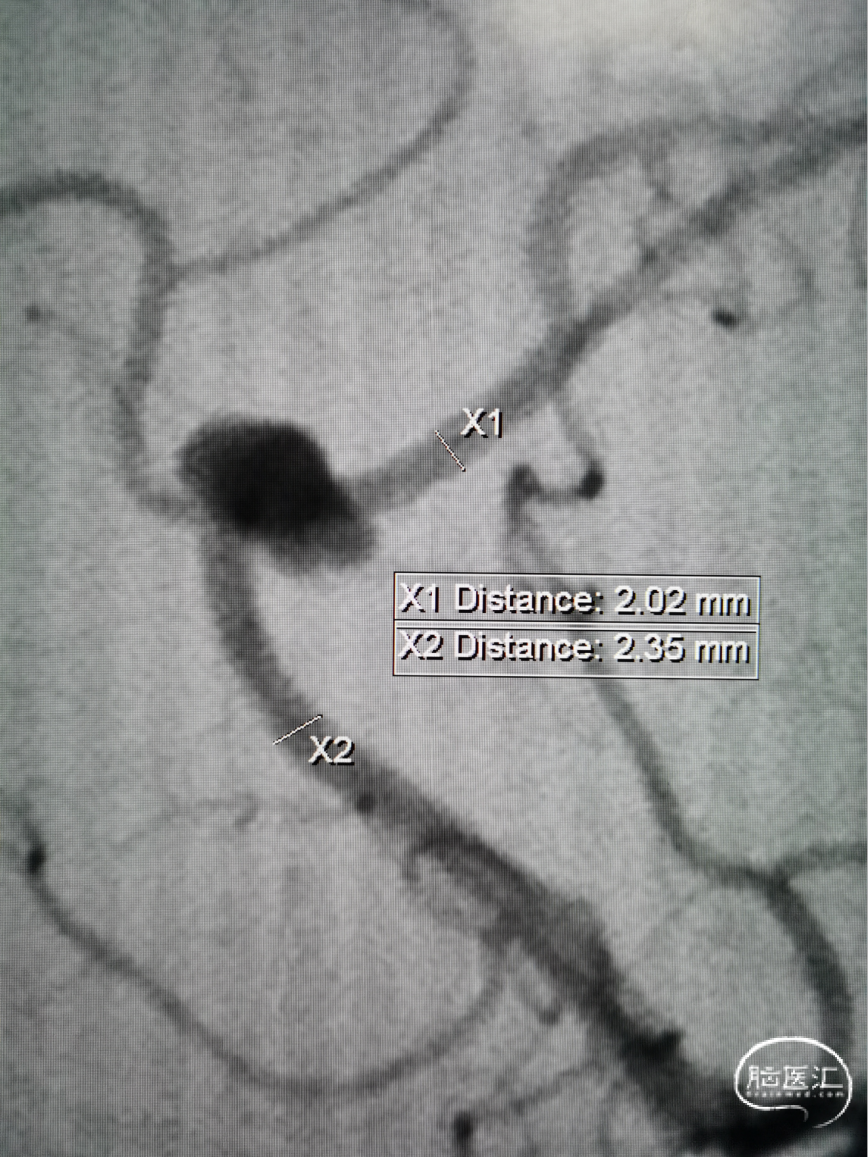

术前测量:

测量动脉瘤瘤体、瘤颈大小,预估支架长度

载瘤动脉直径(mm):远端 2.0;近端 2.4